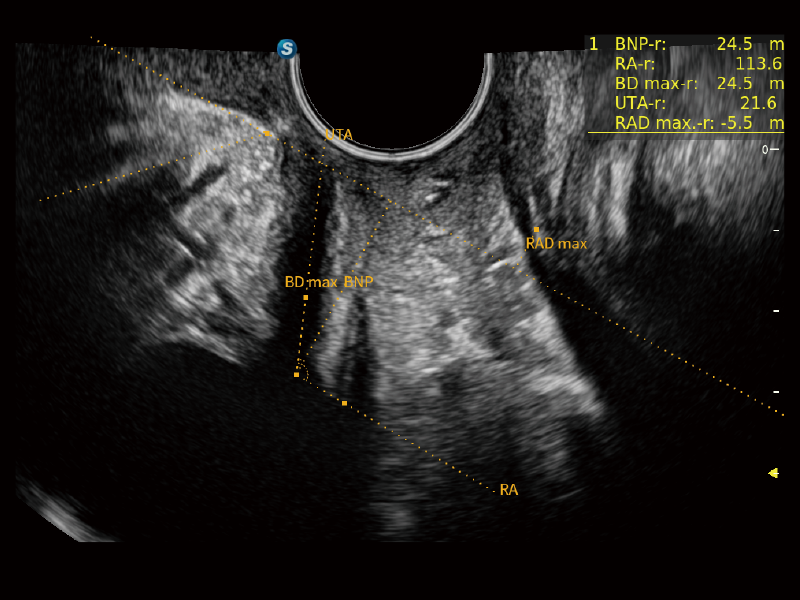

豐富的血流動(dòng)力學(xué)檢測(cè)技術(shù),可在不同醫(yī)療場(chǎng)景中高效捕捉血流信號(hào),助力臨床診療。

在傳統(tǒng)血流的基礎(chǔ)上優(yōu)化掃查和算法策略,能夠更好的抑制組織信息,提煉紅細(xì)胞運(yùn)動(dòng)信息,得到更高幀頻,高靈敏度和分辨率的血流信號(hào),還原更真實(shí)的血流動(dòng)力學(xué)。